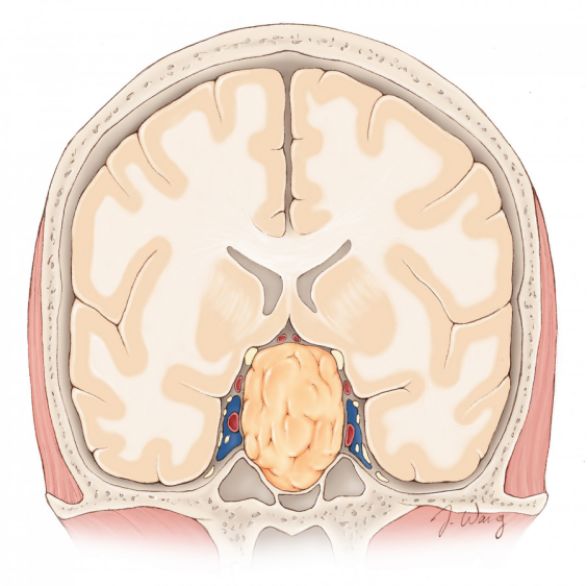

图2. 垂体大腺瘤为直径大于10mm并对周围结构有占位效应的垂体瘤。临床上最常见的压迫症状为压迫视交叉和/或视神经造成双颞侧偏盲。

图3. 图示典型垂体腺瘤矢状位形态。注意垂体受压至肿瘤上方或后方。